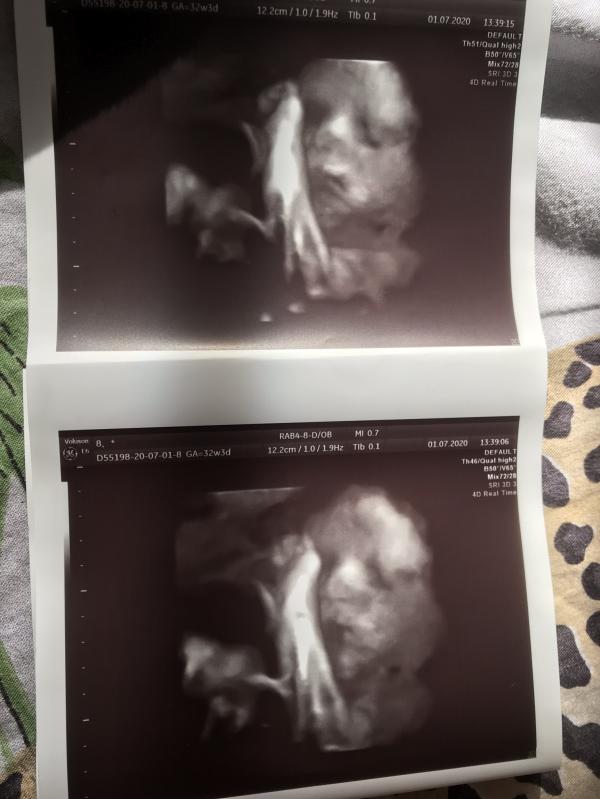

post image 1

post image 2

Однако копия старшего сына у меня в животике🥰🥰🥰мои мальчишки с 10-ти летней разницей